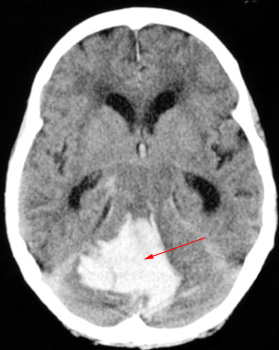

Head CT > Stroke > Hemorrhagic Stroke

Hemorrhagic strokes account for 16% of all strokes. There are two major categories of hemorrhagic stroke. Intracerebral hemorrhage is the most common, accounting for 10% of all strokes. Subarachnoid hemorrhage, due to rupture of a cerebral aneurysm, accounts for 6% of strokes overall.